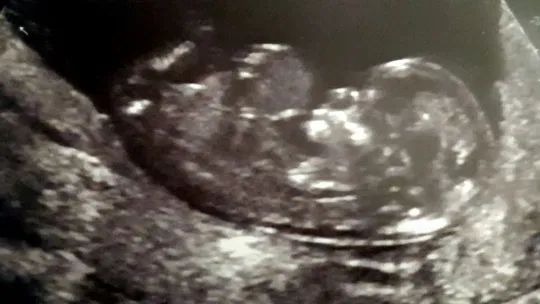

USG Kelly

USG Kelly © Facebook